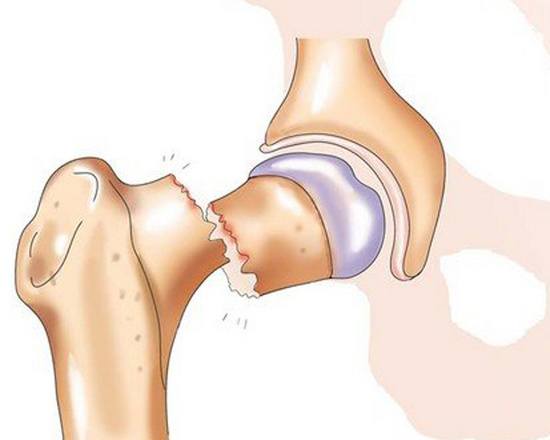

Перелом шейки бедра на рентгенограмме

Тазобедренный сустав – один из самых крупных суставов. Он выполняет опорную функцию и несет значительную нагрузку при беге и ходьбе. Сустав состоит из шаровидной головки бедра и глубокой округлой вертлужной впадины, окруженных капсулой и мощными связками. Еще одна крупная связка располагается прямо в центре сустава и соединяет дно вертлужной впадины с головкой бедра. В своей периферической части головка переходит в шейку, а шейка – в тело бедренной кости. Шейка расположена под углом к основной части кости, в области угла располагаются большой и малый вертелы.

Кровоснабжение головки осуществляется тремя путями. Первый – через сосуды, расположенные в капсуле сустава, второй – через артерии, проходящие внутри кости, и третий – через сосуд, расположенный внутри связки между головкой бедра и вертлужной впадиной. С возрастом кровоснабжение головки бедра ухудшается, сосуды сужаются, а артерия внутри связки полностью закрывается и перестает «работать». При переломах шейки проксимальный отломок лишается питания из внутрикостных сосудов. Артерий в капсуле оказывается недостаточно для адекватного снабжения кости кровью, поэтому проксимальный костный фрагмент не прирастает к дистальному, а в некоторых случаях и вовсе рассасывается. Такое состояние называется аваскулярным некрозом или остеонекрозом шейки и головки бедра.

Перелом шейки бедра на рентгенограмме

Тазобедренный сустав – один из самых крупных суставов. Он выполняет опорную функцию и несет значительную нагрузку при беге и ходьбе. Сустав состоит из шаровидной головки бедра и глубокой округлой вертлужной впадины, окруженных капсулой и мощными связками. Еще одна крупная связка располагается прямо в центре сустава и соединяет дно вертлужной впадины с головкой бедра. В своей периферической части головка переходит в шейку, а шейка – в тело бедренной кости. Шейка расположена под углом к основной части кости, в области угла располагаются большой и малый вертелы.

Кровоснабжение головки осуществляется тремя путями. Первый – через сосуды, расположенные в капсуле сустава, второй – через артерии, проходящие внутри кости, и третий – через сосуд, расположенный внутри связки между головкой бедра и вертлужной впадиной. С возрастом кровоснабжение головки бедра ухудшается, сосуды сужаются, а артерия внутри связки полностью закрывается и перестает «работать». При переломах шейки проксимальный отломок лишается питания из внутрикостных сосудов. Артерий в капсуле оказывается недостаточно для адекватного снабжения кости кровью, поэтому проксимальный костный фрагмент не прирастает к дистальному, а в некоторых случаях и вовсе рассасывается. Такое состояние называется аваскулярным некрозом или остеонекрозом шейки и головки бедра.